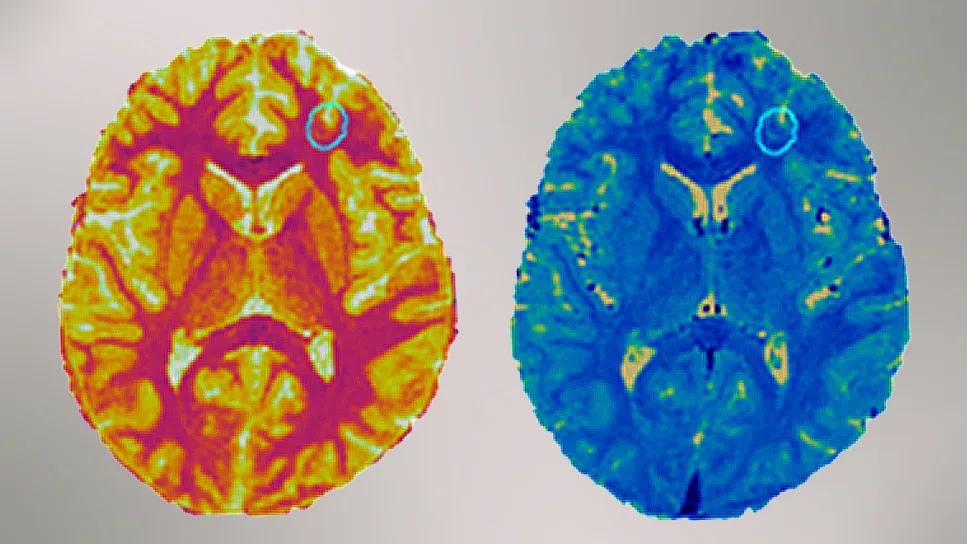

two brightly colored brain scans side by side

two rows of three brain images with varying color schemes

Figure 2. Example patients in whom the MRF T1 shows significant differences in the seizure-causing lesion compared with the electrically “silent” lesion. Knowing this information before surgery could help design better implantation/surgical plans. Reprinted from Kochi et al., J Neurol Sci. 2025;477:12351, ©2025 The Authors, under the CC BY-NC license.